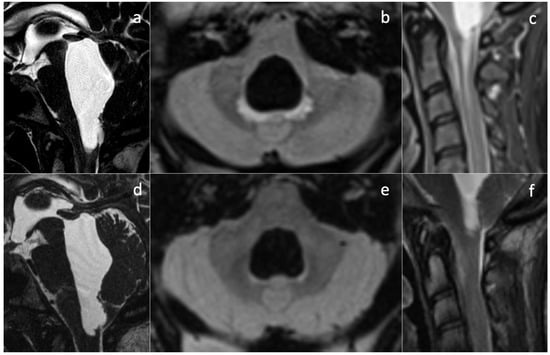

Five months after shunting, continuous and sharp cephalgia arose; MR scans revealed findings suggestive of intracranial hypotension, possibly due to overdrainage (Figure 2a–h). The patient was therefore admitted into hospital, and her shunt was equipped with an anti-siphon device. According to the initial suspicion of overshunting, the valve-opening pressure increased to 200 cmH2O, and eventually, the system was mechanically closed. Despite this, during the patient’s stay, she developed progressive visual impairments, aphasia, and motor incoordination in addition to her pre-existing symptoms, culminating in sensory obnubilation. A few weeks later, a further MR scan showed diffuse demyelination-like alterations of the deep white matter in both hemispheres, along with findings still suggestive of intracranial hypotension, such as collapsed ventricles, dural thickening at the vertex, small sulci, turgidity of dural venous sinuses and brain superficial veins (Figure 2i–p). Insertion of a catheter for ICP monitoring revealed marked intracranial hypertension (50 mmHg). A posteriori evaluation of MR images could not identify any secondary cause of intracranial hypertension. Direct causes of the observed visual impairments were excluded based on MRI examinations, which were persistently negative for optic pathway disease.

Since no MRI sign of intra-cranial hypertension was visible in this examination, the increased ICP found at the time of the new catheter insertion was surprising. The coexistence of collapsed appearance of the lateral ventricles and evidence of correct shunt functioning without overdrainage led to the diagnosis of slit ventricle syndrome. An emergency decompressive craniectomy could not prevent the patient’s death.

Pathophysiological explanations of this condition encompass concurrent mechanisms, such as shunt overdrainage, compensatory venous congestion (as we documented in our case, Figure 2f–h), and altered compliance of the ventricular system and cerebral tissue [8]. In patients with shunt-associated headache, therapeutic management is traditionally based on migraine medication [10] and diuretics [11]. Refractory cases were classified by Panagopoulos et al. [8] into two categories: headache due to intracranial hypotension (overdrainage) and pathological compliance of the ventricular system (classical SVS). In our case, ambiguous MRI findings led to the misclassification of patients in the former category when they actually belonged to the latter. Reduced ventricular compliance masked the diagnosis of intracranial hypertension and favored the misdiagnosis of hypotension. The correct diagnosis of SVS led us to reactivate the shunting device and, eventually, perform a decompressive craniectomy, but this was not timely enough to stop the symptom progression. Notably, the physiology of CSF intra- and extra-ventricular circulation was preserved. Orthodromic circulation was present from the choroid plexus in the ventricles to the arachnoid granulations, without obstructive phenomena at any stage. CSF shunting was necessary to counteract intracranial pressure increase, worsened by reduced ventricular wall compliance. The treatments we performed included all of the widely accepted recommendations for headache due to intracranial hypotension, namely: (1) the addition of an anti-siphon device; (2) an increase in valve opening pressure; (3) a combination of both in refractory cases; and (4) careful check of the ventricular catheter and replacement in cases of obstruction [8]. Treatment of proper SVS, with pathological compliance of the ventricular system, is more controversial. Proposed interventions are highly heterogeneous and include shunt revision/repositioning/substitution, third ventriculostomy, an increase in valve opening pressure, and decompressive surgery [8,12]. This is because appropriate treatment should be provided according to the underlying pathophysiological context, not the epiphenomenon of altered ventricular compliance. Endoscopic third ventriculostomy can be appropriate in cases of raised ICP and obstructive hydrocephalus; shunt revision when obstruction is exacerbating ICP increase in combination with altered ventricular compliance; and increase in valve opening pressure in shunted children where dampened CSF pressure waves have induced abnormal calvarial synostosis [13]. Further research is needed to clarify the emerging role of the glymphatic system in IIH pathogenesis [14,15] in order to propose less invasive and disease-modifying treatments. To the best of our knowledge, no medical treatment targeting aquaporin-4 changes or neurogliovascular unit disruption in IIH has ever been developed, currently leaving no alternatives to surgical treatments—and complications.

Figure 2. Post-shunting MRI scans. The first post-operative MRI (ah) is highly suggestive of intracranial hypotension, with “slumping midbrain” and depression of the vena magna Galeni (a), small ventricles (b), and supra- and sub-tentorial dural thickening with turgidity of the venous sinuses (fh). At the same time, a fluid effusion surrounds the parenchymal course of the catheter, hinting at draining dysfunction. DWI sequences did not show abnormal findings (e). MR scan after marked neurological deterioration (ip) shows ongoing demyelination of deep periventricular white matter in both hemispheres (ik). Radiological signs suggestive of intra-cranial hypotension are even more conspicuous here than previously described in images (ah).